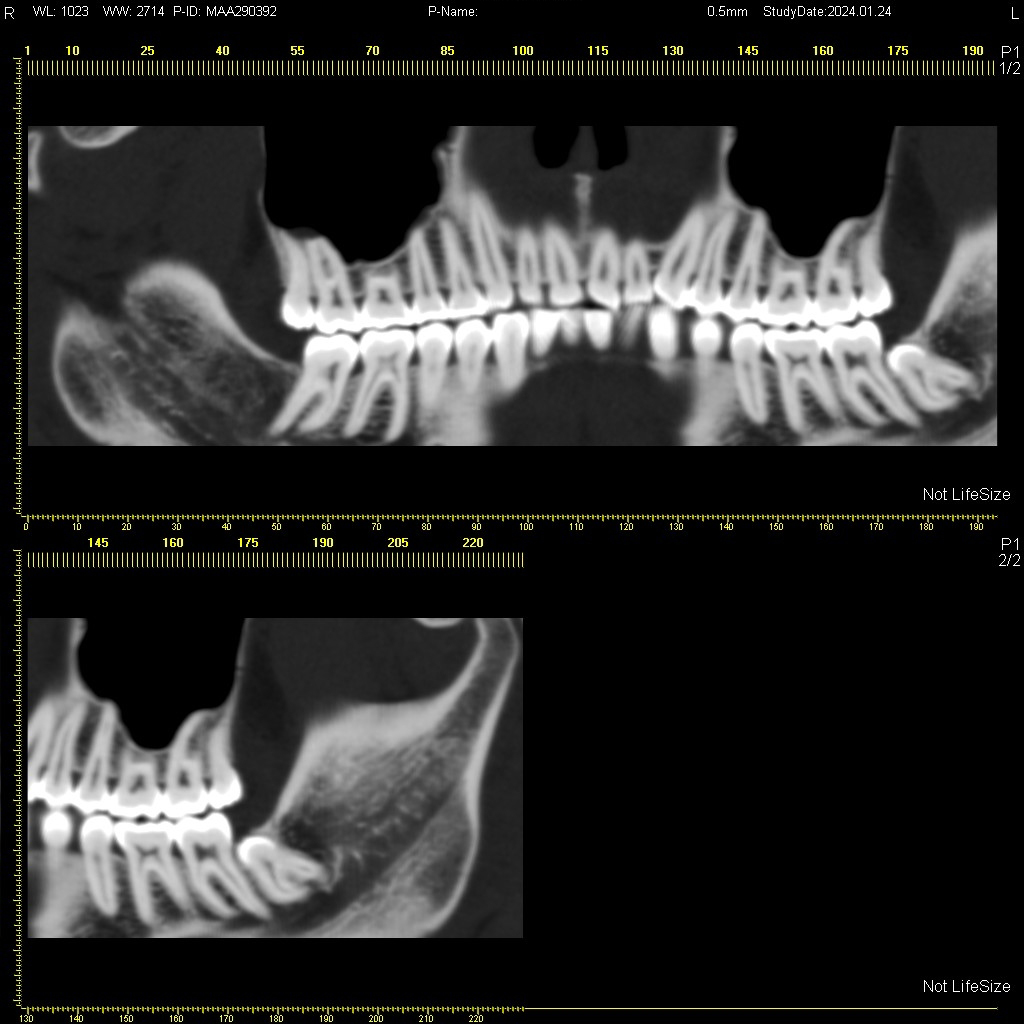

Мультиспиральная дентальная компьютерная томография (МДКТ или, как ее еще называют, КТ зубов) – это современный высокоточный метод лучевой диагностики, с помощью которого получают объемные цифровые изображения всей зубочелюстной системы. В основе метода лежит применение рентгеновского излучения и последующая цифровая обработка полученных данных специальными компьютерными программами.

Мультиспиральный томограф выполняет послойное сканирование области верхней и нижней челюстей с помощью рентгеновских лучей, а затем, используя компьютерную обработку данных, создает 3D-модели исследуемой зоны. Современные модели томографов проводят круговое сканирование по спирали, делая срезовые снимки на расстоянии 0,5 мм друг от друга. Затем на основе этих данных реконструируются детальные изображения челюстно-лицевой области в трехмерном формате.

В отличие от конусно-лучевой компьютерной томографии (КЛКТ), которая также в последнее время применяется в стоматологии, МДКТ помогает лучше визуализировать костные структуры на фоне артефактов от имплантов и протезов, выполнить сканирование быстрее, без двигательных артефактов, в любом объеме под запрос вашего ортодонта.

- Информативность. Дентальная КТ позволяет обнаружить признаки патологии, которые не видны на обычных (2D) панорамных снимках – ортопантомограммах. На двухмерных рентгенограммах различные структуры накладываются друг на друга. В отличие от этого пространственные модели дают возможность рассмотреть челюстно-лицевой аппарат в различной проекции и плоскости.

- Широкие возможности диагностики. На трехмерных изображениях можно увидеть в целом верхнюю и нижнюю челюсть, включая гайморовы пазухи, височно-нижнечелюстные суставы. Помимо костной ткани при проведении КТ можно оценить состояние окружающих мягких тканей. Это бывает особенно важно при выборе оптимального способа протезирования и имплантации, при подозрении на опухолевые процессы, при планировании оперативного вмешательства.

Исследование занимает всего пару минут. Данные, полученные при сканировании, проходят цифровую обработку и выводятся на монитор компьютера в виде 3D-изображений. Врач-рентгенолог внимательно анализирует данные и выдает заключение.

Высокая информативность исследования за счет детальных снимков и наглядных пространственных 3D-реконструкций позволяет увидеть то, что недоступно для визуального осмотра и обычного рентгеновского обследования.

Дентальная КТ показывает: